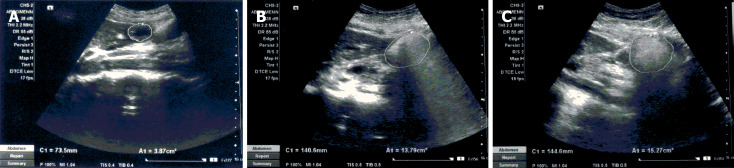

Methods: Thirty healthy volunteers (17 males, age: 29.4 ± 6.0 years, body mass index: 23.4 ± 2.94 and 13 females, age: 37.2 ± 11.9 years, body mass index: 22.9 ± 4.34) underwent gastric emptying by real-time ultrasonography after a solid meal and a comparable commercially prepared semi-solid meal (each meal, total calorie 350 kcal, carbohydrates 60%, fat 30% and proteins 10%), on separate dates 1 week apart. The gastric antral area was measured at 5 minutes, 15 minutes, 30 minutes, 45 minutes, 60 minutes, 90 minutes, 120 minutes, 150 minutes, 180 minutes, 210 minutes, and 240 minutes post-ingestion using a previously validated technique and compared between meals.